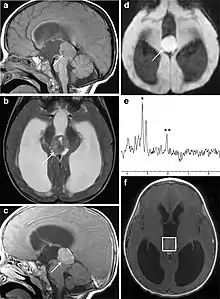

Several imaging methods can be used to diagnose pineoblastoma. Initially, urgent CTs are recommended, followed by MR imaging.[13] CT will show large, multilobulated masses with heterogenous contrast enhancement and peripheral calcification of the pineal gland.[4][3] On MRI, pineoblastomas again appear as masses with heterogenous enhancement. They often appear hypo- to isointense on T1 and slightly hyperintense on T2-weighted images. Some areas of necrosis or hemorrhage may be seen as well. PET-CT has also been used in diagnosis, and shows increased uptake of fludeoxyglucose with pineoblastomas compared to other pineal masses.